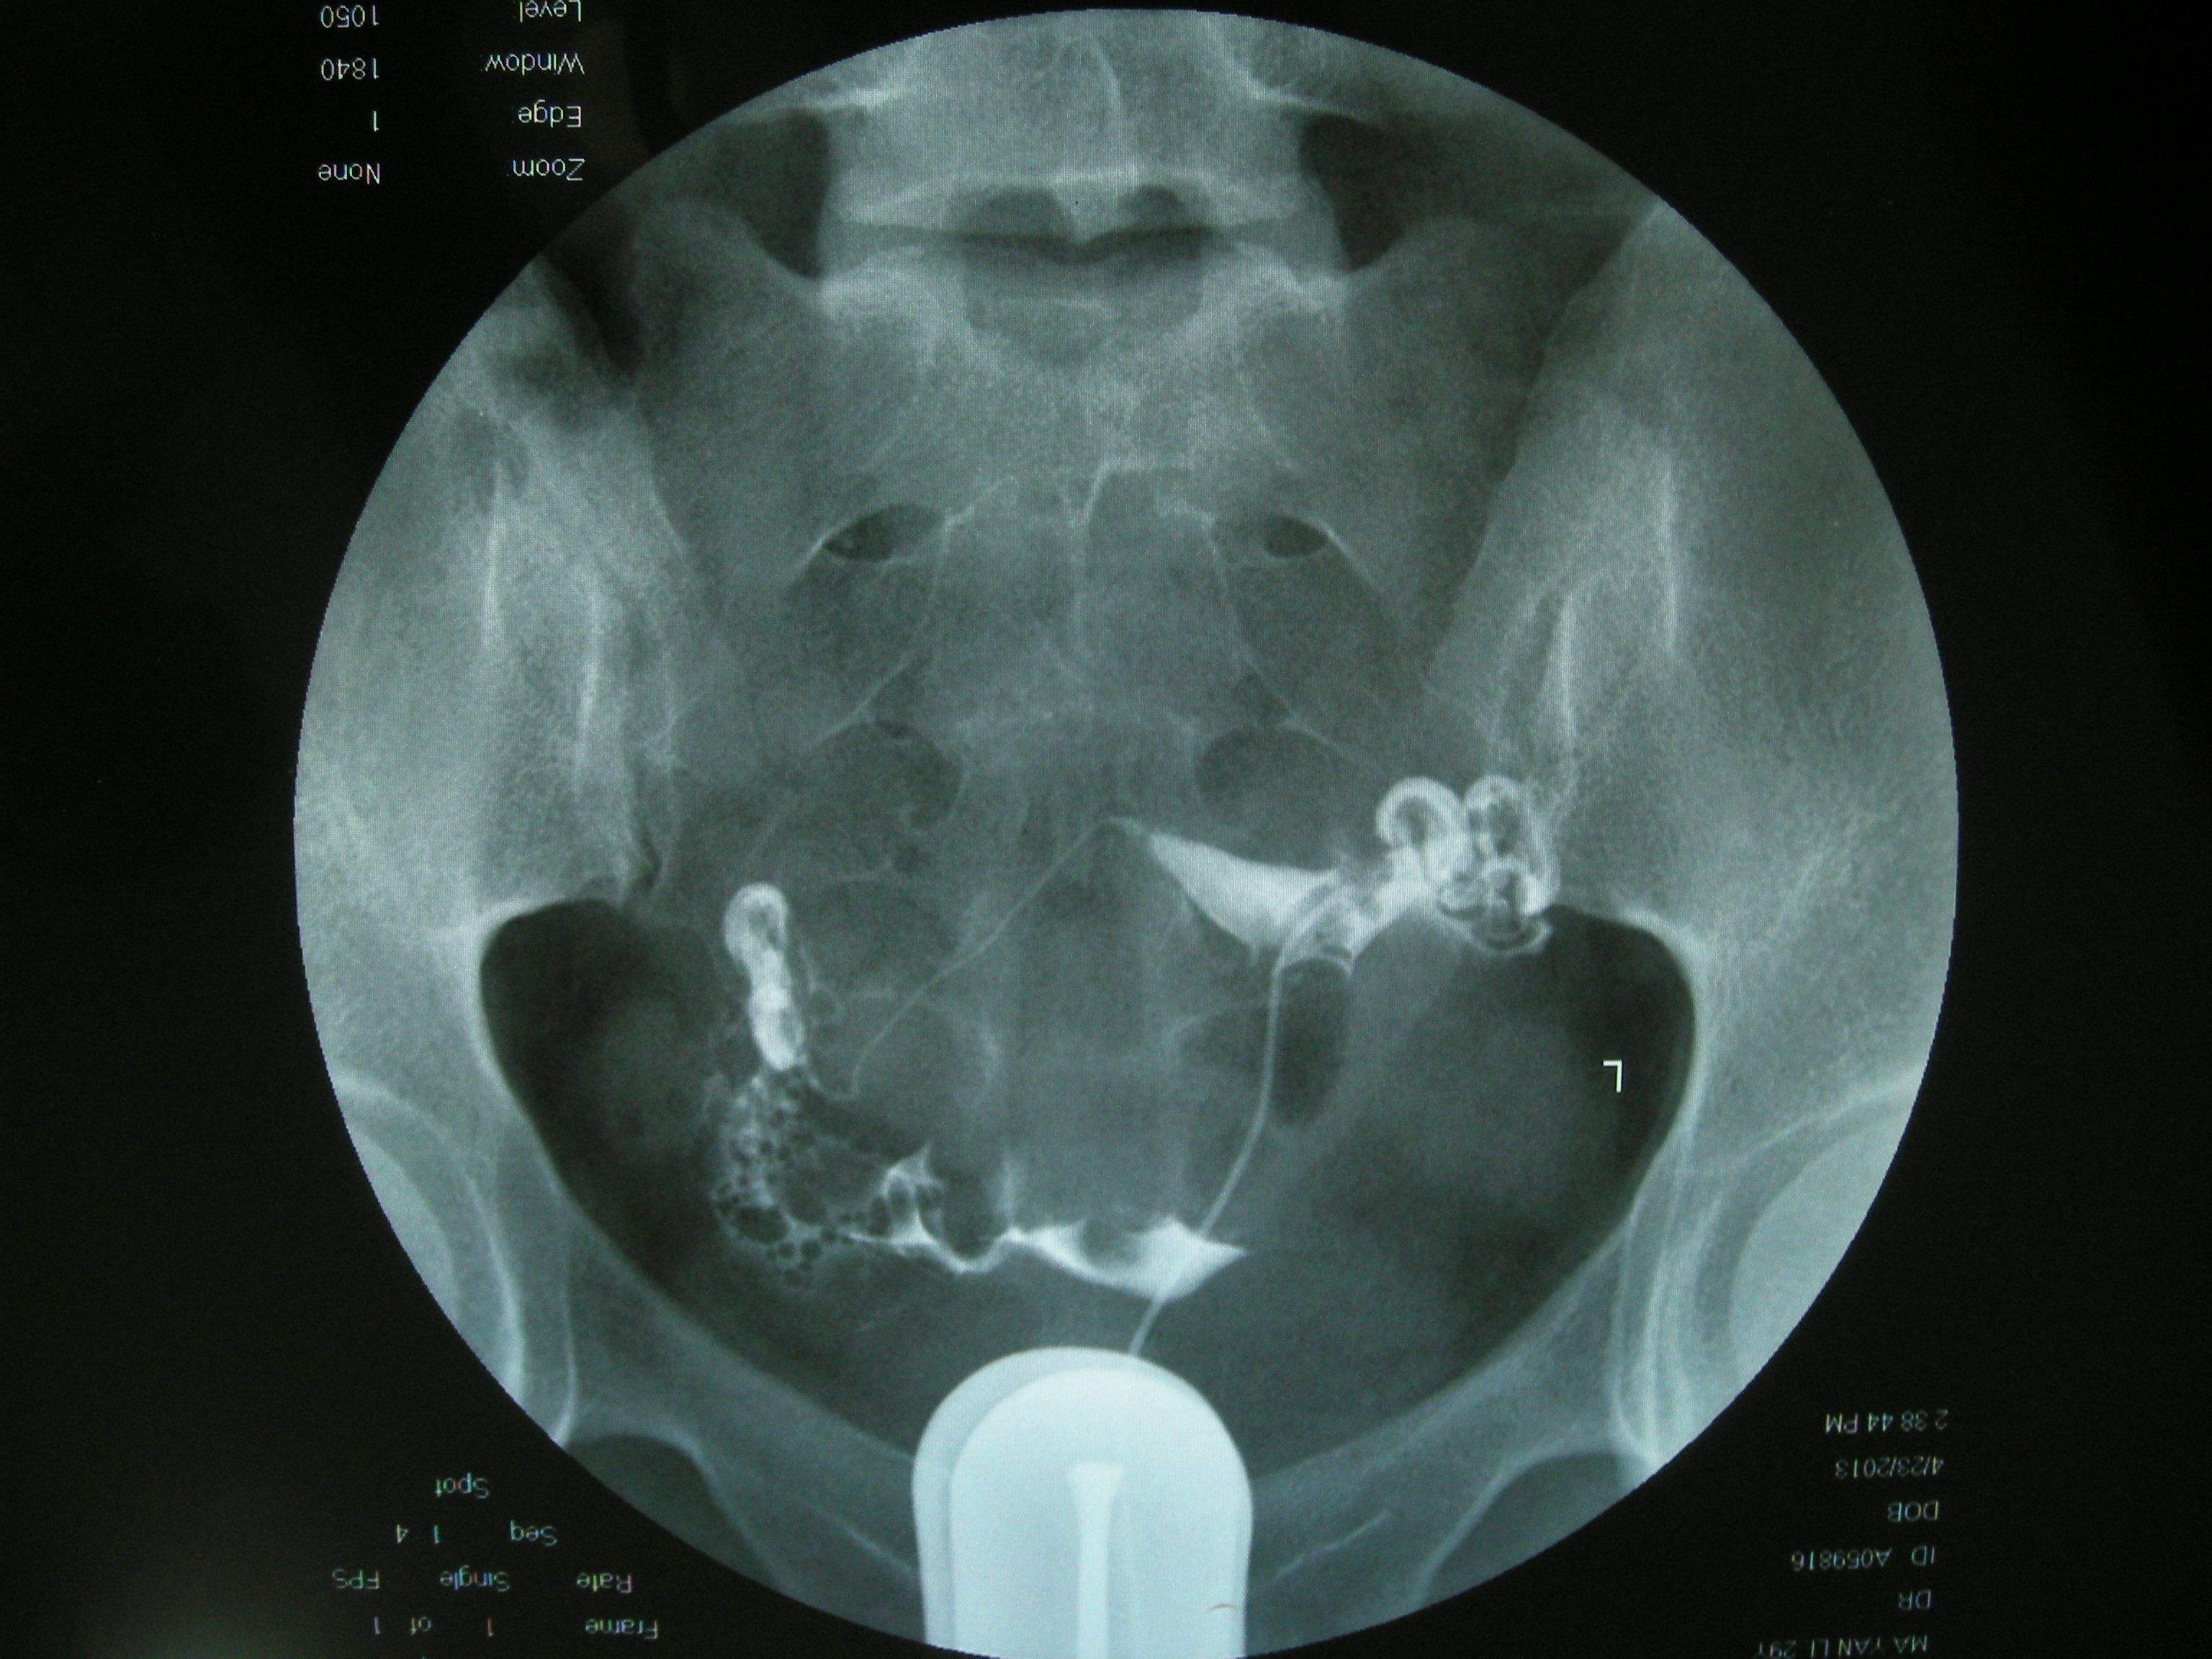

第三步:在X线透视下观察造影剂流经宫腔,在荧光的透视下慢慢注入碘油,注入量第一次为3~5ML,观察其进入子宫及流经输卵管的情况,此时会拍摄一张照片然后会继续推入碘油,5--10分钟后继续拍片。

第四步:一天之后再在同部位拍摄,然后观察腹腔内是否有游离的碘海醇,如果双侧输卵管不通,那么盆腔内就不会有碘油,如果只有少量碘海醇那么就可以认为是输卵管通而不畅。